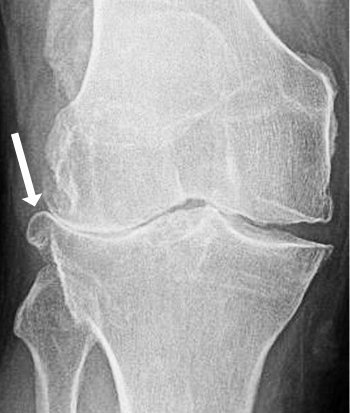

Osteophyte in an osteoarthritic knee.

Bone is in constant flux, with bone being broken down in some areas and generated in others. Sometimes an imbalance forms and a spur of excess bone develops at an edge. This is called an 'osteophyte' or 'bone mushroom'. Large osteophytes are associated with knee pain and osteoarthritis progression. Small ones in younger patients seem to be transient.

In bones that are under mechanical stress, such as in osteoarthritis, larger osteophytes may be triggered, again at the lip of the joint.